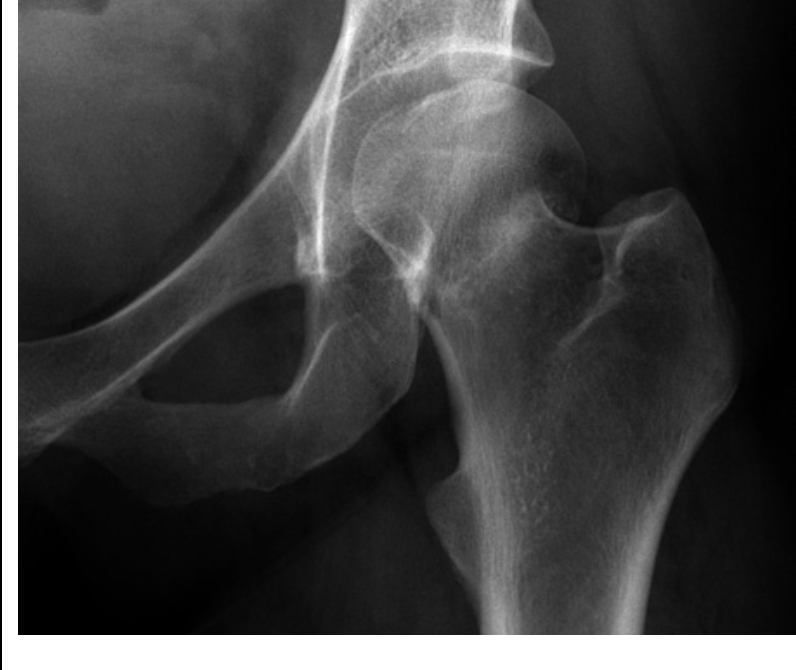

Intracapsular fracture - Subcapital - AP:

1. Shortened femoral neck

2. Increased density of femoral neck (due to impacted bone)

3. Less troch. is more prominent

4. Shenton’s line is disrupted